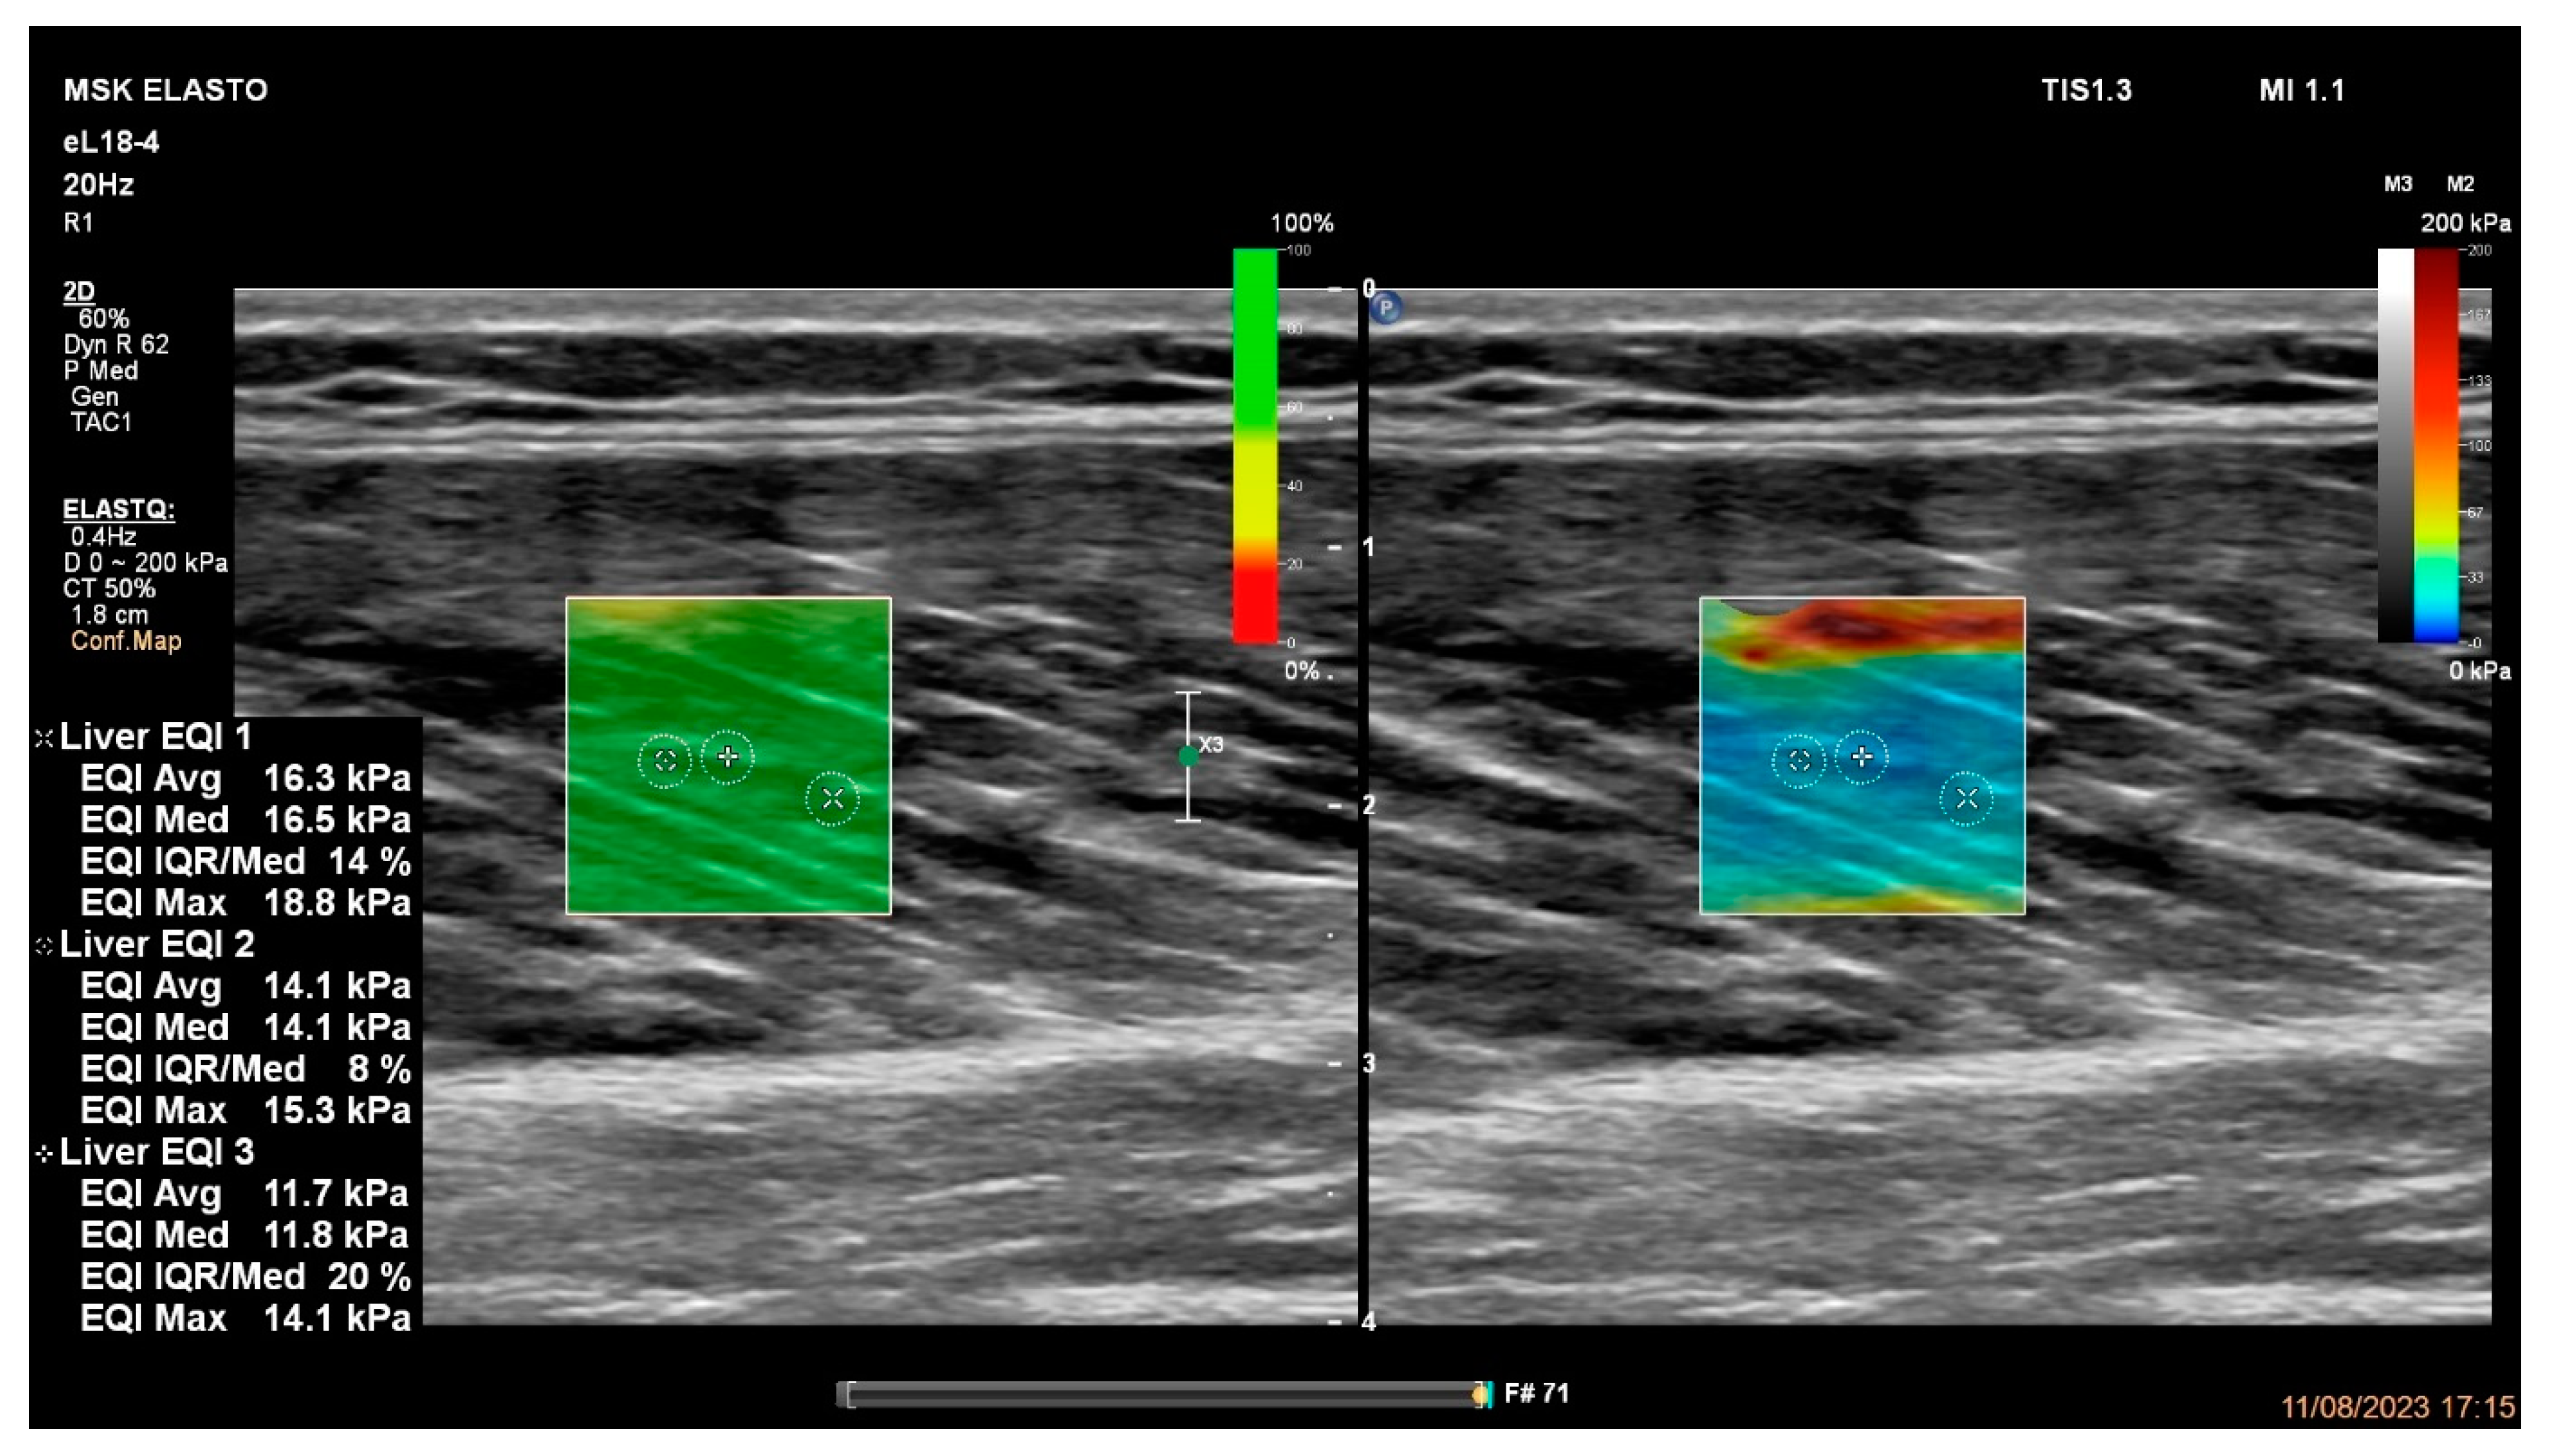

2.4. Hamstring Muscles’ Passive Stiffness Measurements